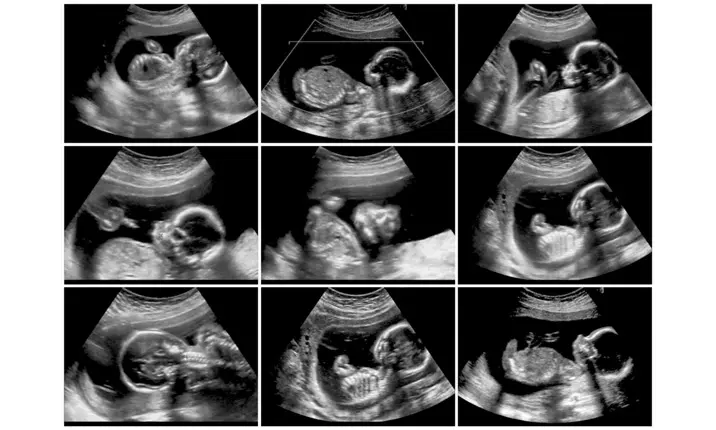

Pregnancy is a beautiful journey, but it also requires proper medical care to ensure the health of both mother and baby. One of the most important parts of pregnancy care is regular medical testing. Many women often ask which tests are required, when they are needed, and why they are important. This blog explains Pregnancy Tests During Pregnancy in very simple language. You will also learn about pregnancy tests month wise, including ultrasound scans and laboratory tests that help doctors monitor a healthy pregnancy. At Malti Hospital & Test Tube Baby Centre, we guide expecting mothers with proper antenatal testing and expert care throughout pregnancy. Why Are Pregnancy Tests During Pregnancy Important? Pregnancy tests help doctors: Check the health of the mother Monitor baby’s growth and development Detect problems early Prevent pregnancy complications Regular Pregnancy Tests During Pregnancy help ensure a safe pregnancy and timely treatment if needed. What Are Pregnancy Tests? Pregnancy tests include: Blood tests Urine tests Ultrasound scans These tests are done at different stages of pregnancy. Doctors plan them carefully based on the pregnancy month and medical condition. Understanding pregnancy tests month wise helps mothers feel confident and stress-free. Pregnancy Tests Month Wise – Complete Breakdown Below is a clear and simple explanation of pregnancy tests by trimester. First Trimester Pregnancy Tests (0–3 Months) The first trimester is very important because the baby’s organs start forming during this time. Blood Tests in First Trimester Hemoglobin test (to check anemia) Blood group & Rh factor Blood sugar test Thyroid test HIV, Hepatitis B & other infection tests These are essential Pregnancy Tests During Pregnancy to ensure the mother is healthy. Urine Tests Routine urine examination Urine infection test Urine tests help detect infections and kidney issues early. Ultrasound in First Trimester Dating scan (to confirm pregnancy and due date) NT Scan (Nuchal Translucency) NT scan checks the baby’s early development and risk of genetic problems. Second Trimester Pregnancy Tests (4–6 Months) This trimester focuses on baby’s growth and structure. Blood Tests Repeat hemoglobin test Blood sugar test (gestational diabetes screening) These Pregnancy Tests During Pregnancy help prevent complications like diabetes. Ultrasound in Second Trimester Anomaly Scan (detailed baby scan) The anomaly scan checks: Baby’s organs Spine, heart, brain Placenta position This is one of the most important pregnancy tests month wise. Third Trimester Pregnancy Tests (7–9 Months) The third trimester focuses on baby’s growth, position, and delivery planning. Blood Tests Hemoglobin test Blood sugar monitoring Infection screening (if required) Ultrasound in Third Trimester Growth Scan Color Doppler Scan (if advised) These scans check: Baby’s weight Blood flow to baby Placenta health Such Pregnancy Tests During Pregnancy help doctors decide the safest delivery plan. Common Ultrasound Tests During Pregnancy Ultrasound scans are safe and painless. Main Ultrasound Scans Include Dating Scan NT Scan Anomaly Scan Growth Scan Color Doppler Scan These scans play a major role in pregnancy tests month wise planning. Important Lab Tests During Pregnancy Lab tests are done to monitor mother’s health. Common Lab Tests Hemoglobin test Blood sugar test Thyroid test Urine routine test Infection screening tests Regular lab testing is a key part of Pregnancy Tests During Pregnancy. High-Risk Pregnancy and Extra Tests Some women need extra tests if pregnancy is high risk due to: High blood pressure Diabetes Thyroid disorder IVF pregnancy Age above 35 In such cases, doctors may advise more frequent Pregnancy Tests During Pregnancy. Expert Guidance by Dr. Malti Bhojwani Pregnancy care and testing at Malti Hospital is guided by Dr. Malti Bhojwani, a senior Obstetrician and Gynecologist with 40+ years of experience. Dr. Malti Bhojwani has managed thousands of normal and high-risk pregnancies. She believes in clear communication and ensures that every mother understands her pregnancy tests month wise without fear or confusion. Why Choose Malti Hospital for Pregnancy Tests During Pregnancy? Expecting mothers trust us because we offer: Complete antenatal testing under one roof Advanced ultrasound facilities Accurate lab reports Experienced gynecologist supervision Clean, safe, and comfortable environment This makes Malti Hospital a reliable choice for Pregnancy Tests During Pregnancy. Serving Bhopal and Nearby Areas We provide pregnancy care and testing to patients from: Arera Colony MP Nagar Kolar Road BHEL Shahpura Ayodhya Nagar Hoshangabad Road Misrod New Market Patients from nearby towns also visit us for trusted pregnancy care. Do All Pregnant Women Need the Same Tests? Most tests are common for all women, but some tests may vary depending on: Medical history Age Pregnancy type Previous pregnancy issues Doctors decide the exact pregnancy tests month wise plan individually. Tips for Expecting Mothers Never skip recommended tests Attend regular antenatal checkups Ask questions if you are confused Follow doctor’s advice strictly Proper testing ensures a safer pregnancy. Conclusion Understanding Pregnancy Tests During Pregnancy helps expecting mothers feel confident and prepared. Month-wise testing, combined with expert medical care, ensures early detection of problems and supports a healthy pregnancy. If you are looking for proper guidance on pregnancy tests month wise, consult experienced specialists at Malti Hospital for safe and reliable care.